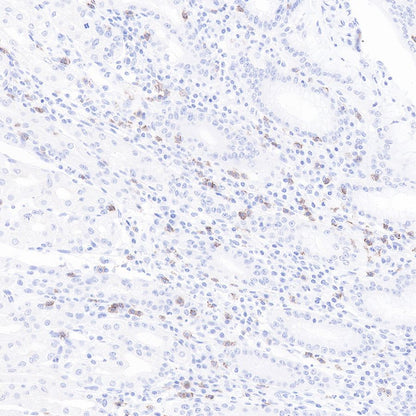

IHC shows positive staining in paraffin-embedded human stomach.

CD8α Mouse mAb was used at 1/1000 dilution, followed by a Goat Anti-mouse IgG H&L (HRP) ready to use.

Counterstained with hematoxylin.

Heat mediated antigen retrieval with Tris/EDTA buffer pH9.0 was performed before commencing with IHC staining protocol.